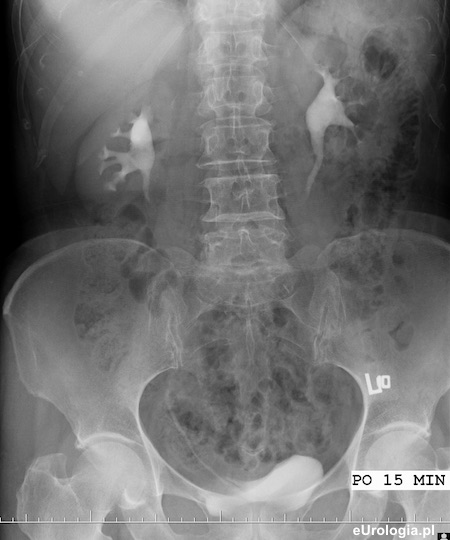

Zdjęcie urograficzne po 15 minutach - widoczny zakontrastowany mocz w UKM obu nerek, dolny odcinek prawego moczowodu i słabo wypełniony pęcherz moczowy.